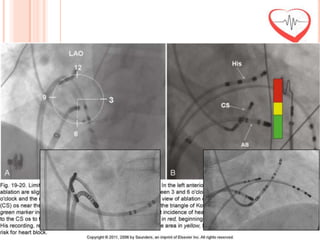

ABLATION SITE

 Amplitude A:V = 1:5

 (Small A and big V)

 Each ablation: 10 to 20 seconds

PREVENTING ATRIOVENTRICULAR BLOCK

Ablation sites below triangle of Koch           Inferior to level of CS roof                 Standard practice